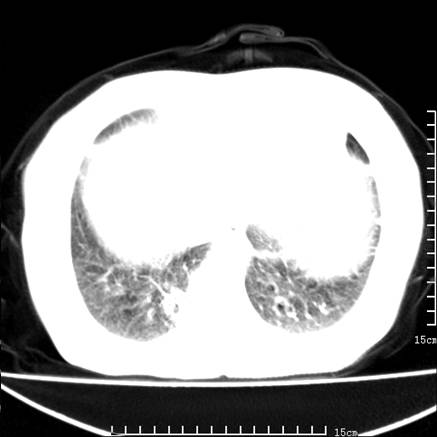

女,王某,58岁,咳嗽三个月余,基层医院二个月前诊为肺结核,用抗结核药二个月无明显疗效。

心包积液致肺瘀血.右侧周围型肺癌伴肺内转移,中间裂积液,叶间胸膜肥厚.右上肺大泡,右侧胸膜肥厚.

双肺继发型tb,心功能不全并肺淤血、心包、双侧叶间裂积液,肺大泡,右下胸膜肥厚钙化。